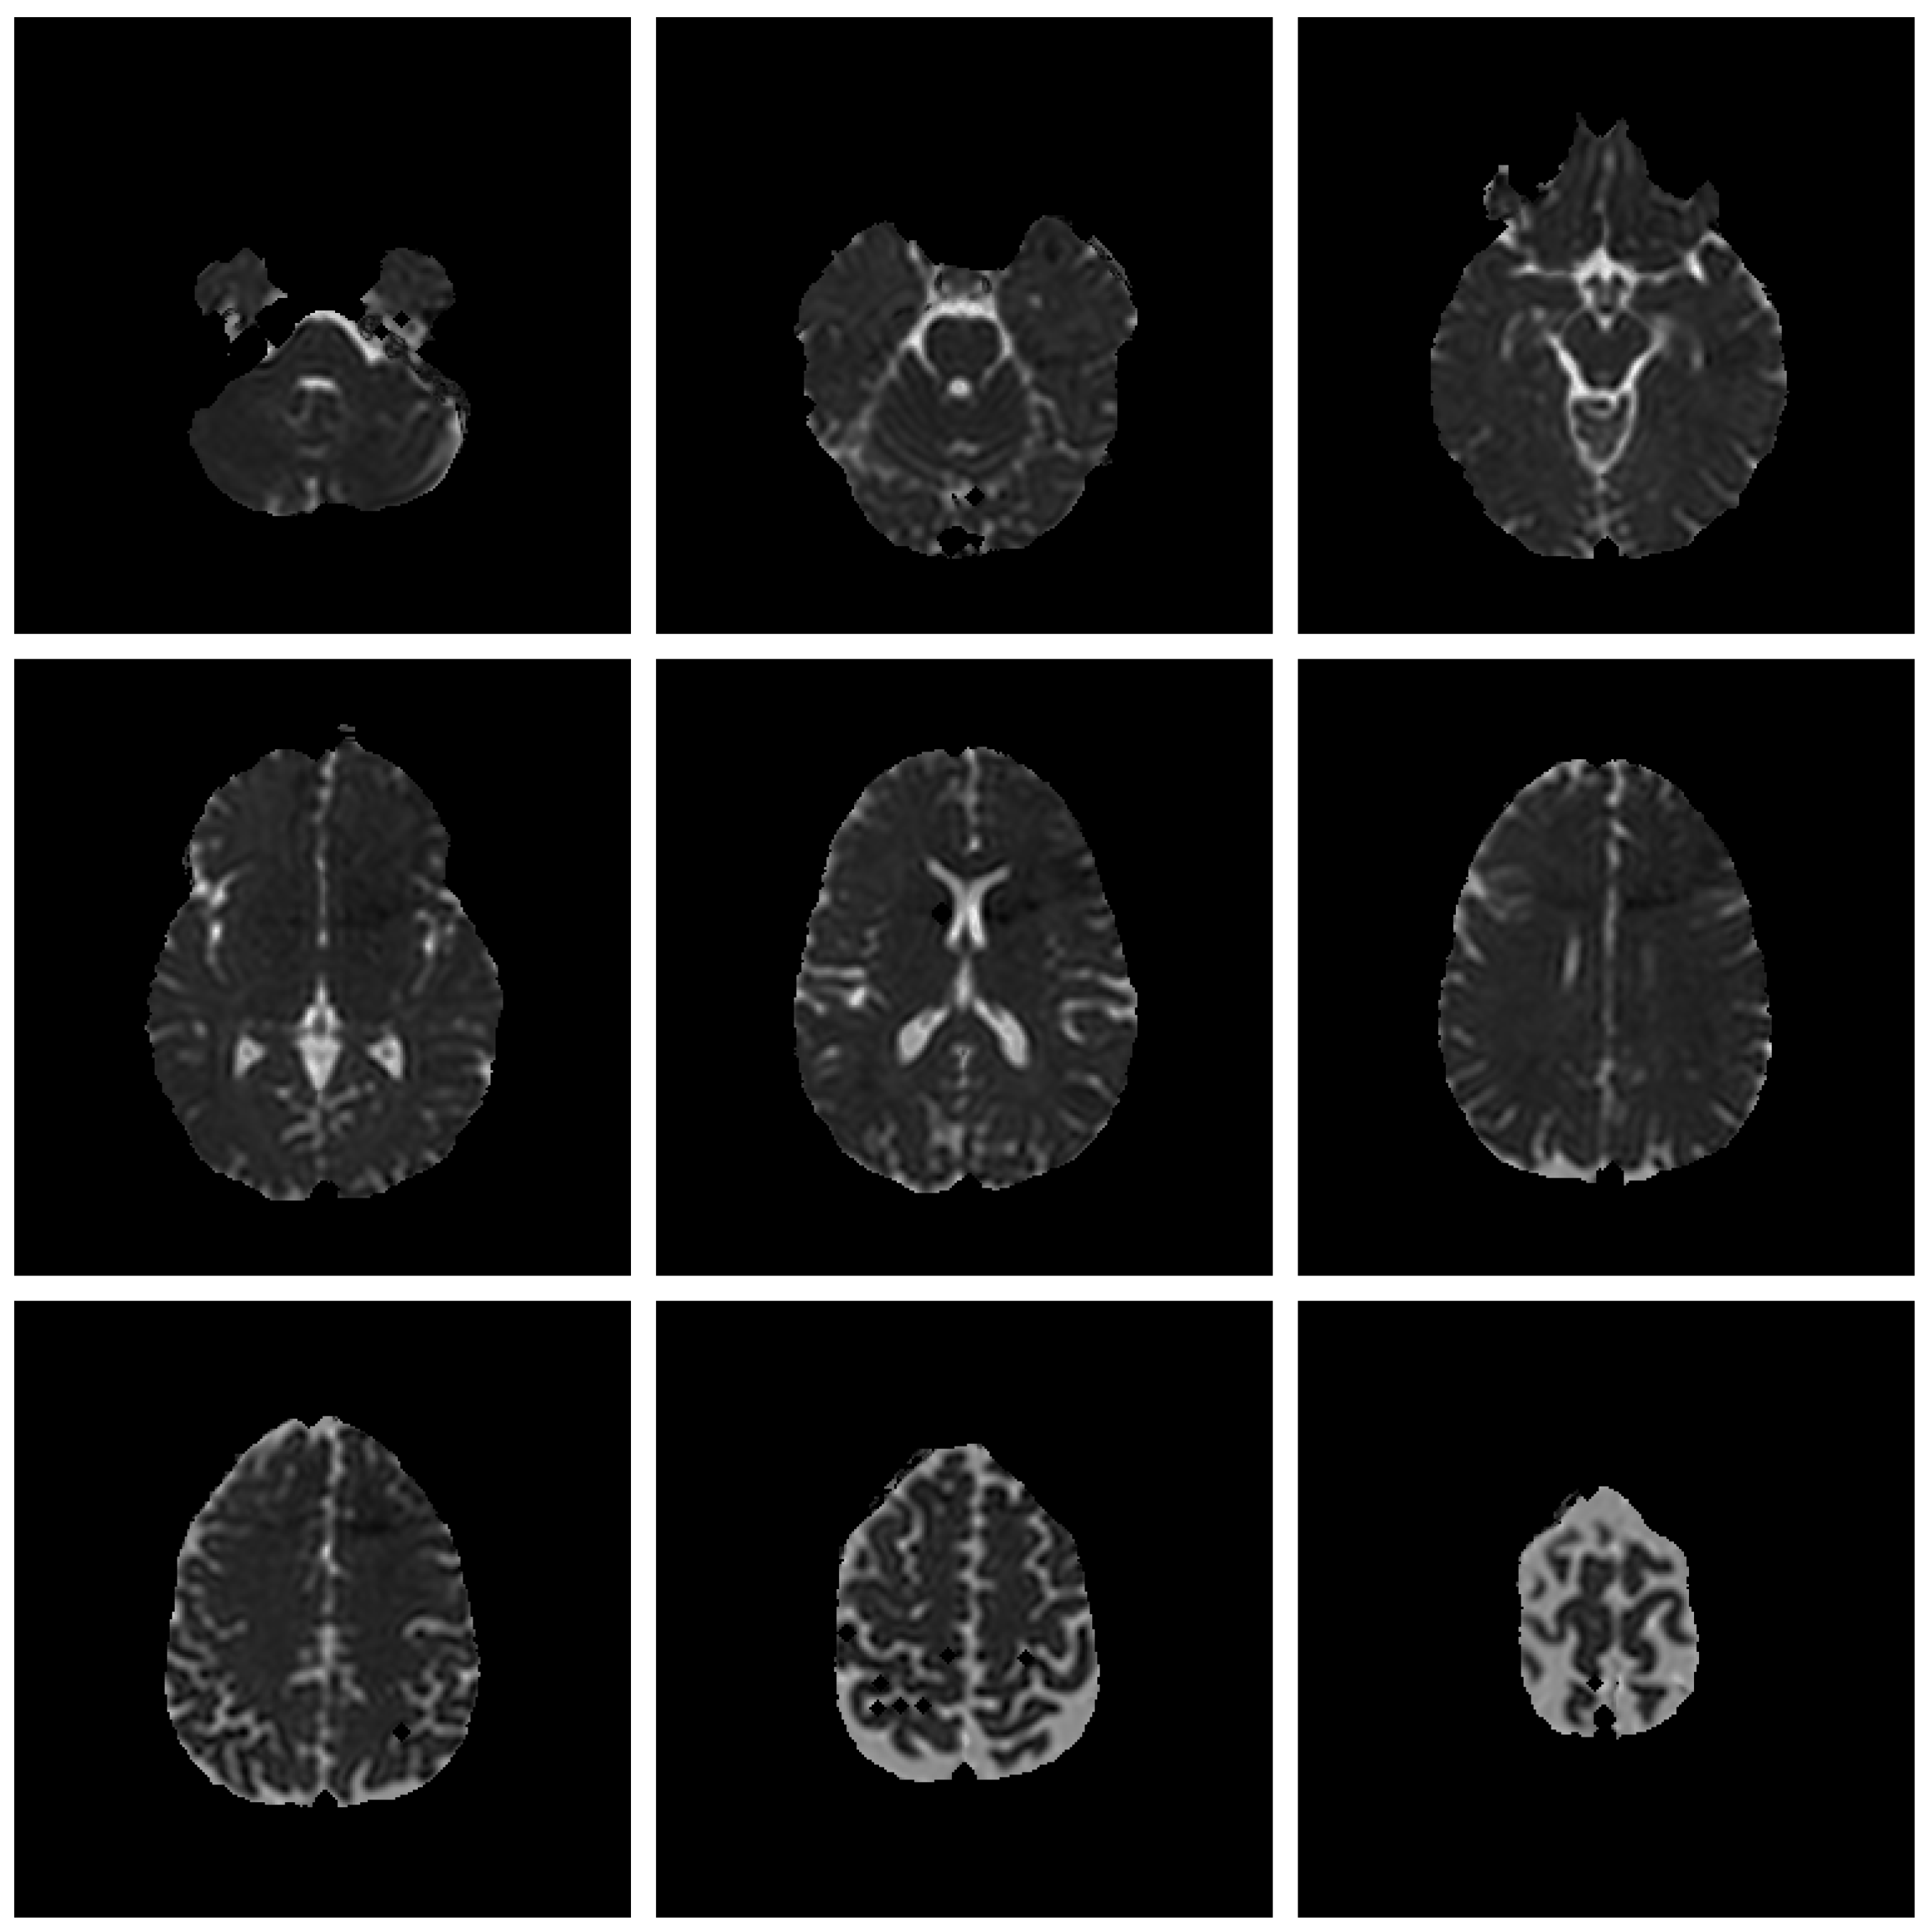

3.2. Image Segmentation Utility

- Generate the WM/non-WM file: Select FA, apply Histogram Quantization with 3 clusters, and save the binary file of the clustered image.

- Generate the CSF/non-CSF file: Select MD, apply Histogram Quantization with 3 clusters, and save the binary file of the clustered image.

- Generate the entire tissues file (GM is non-WM and non-CSF): Select MD, apply Threshold clustering with value 2, and save the binary file of the threshold image.

- Load WM/non-WM file as Layer 1 (Top Layer), CSF/non-CSF file as Layer 2 and the entire tissues file as layer 3.

- Once you unselect one of the clusters check boxes, the cluster will not be included in the layer and its space will be available for the other lower layers.